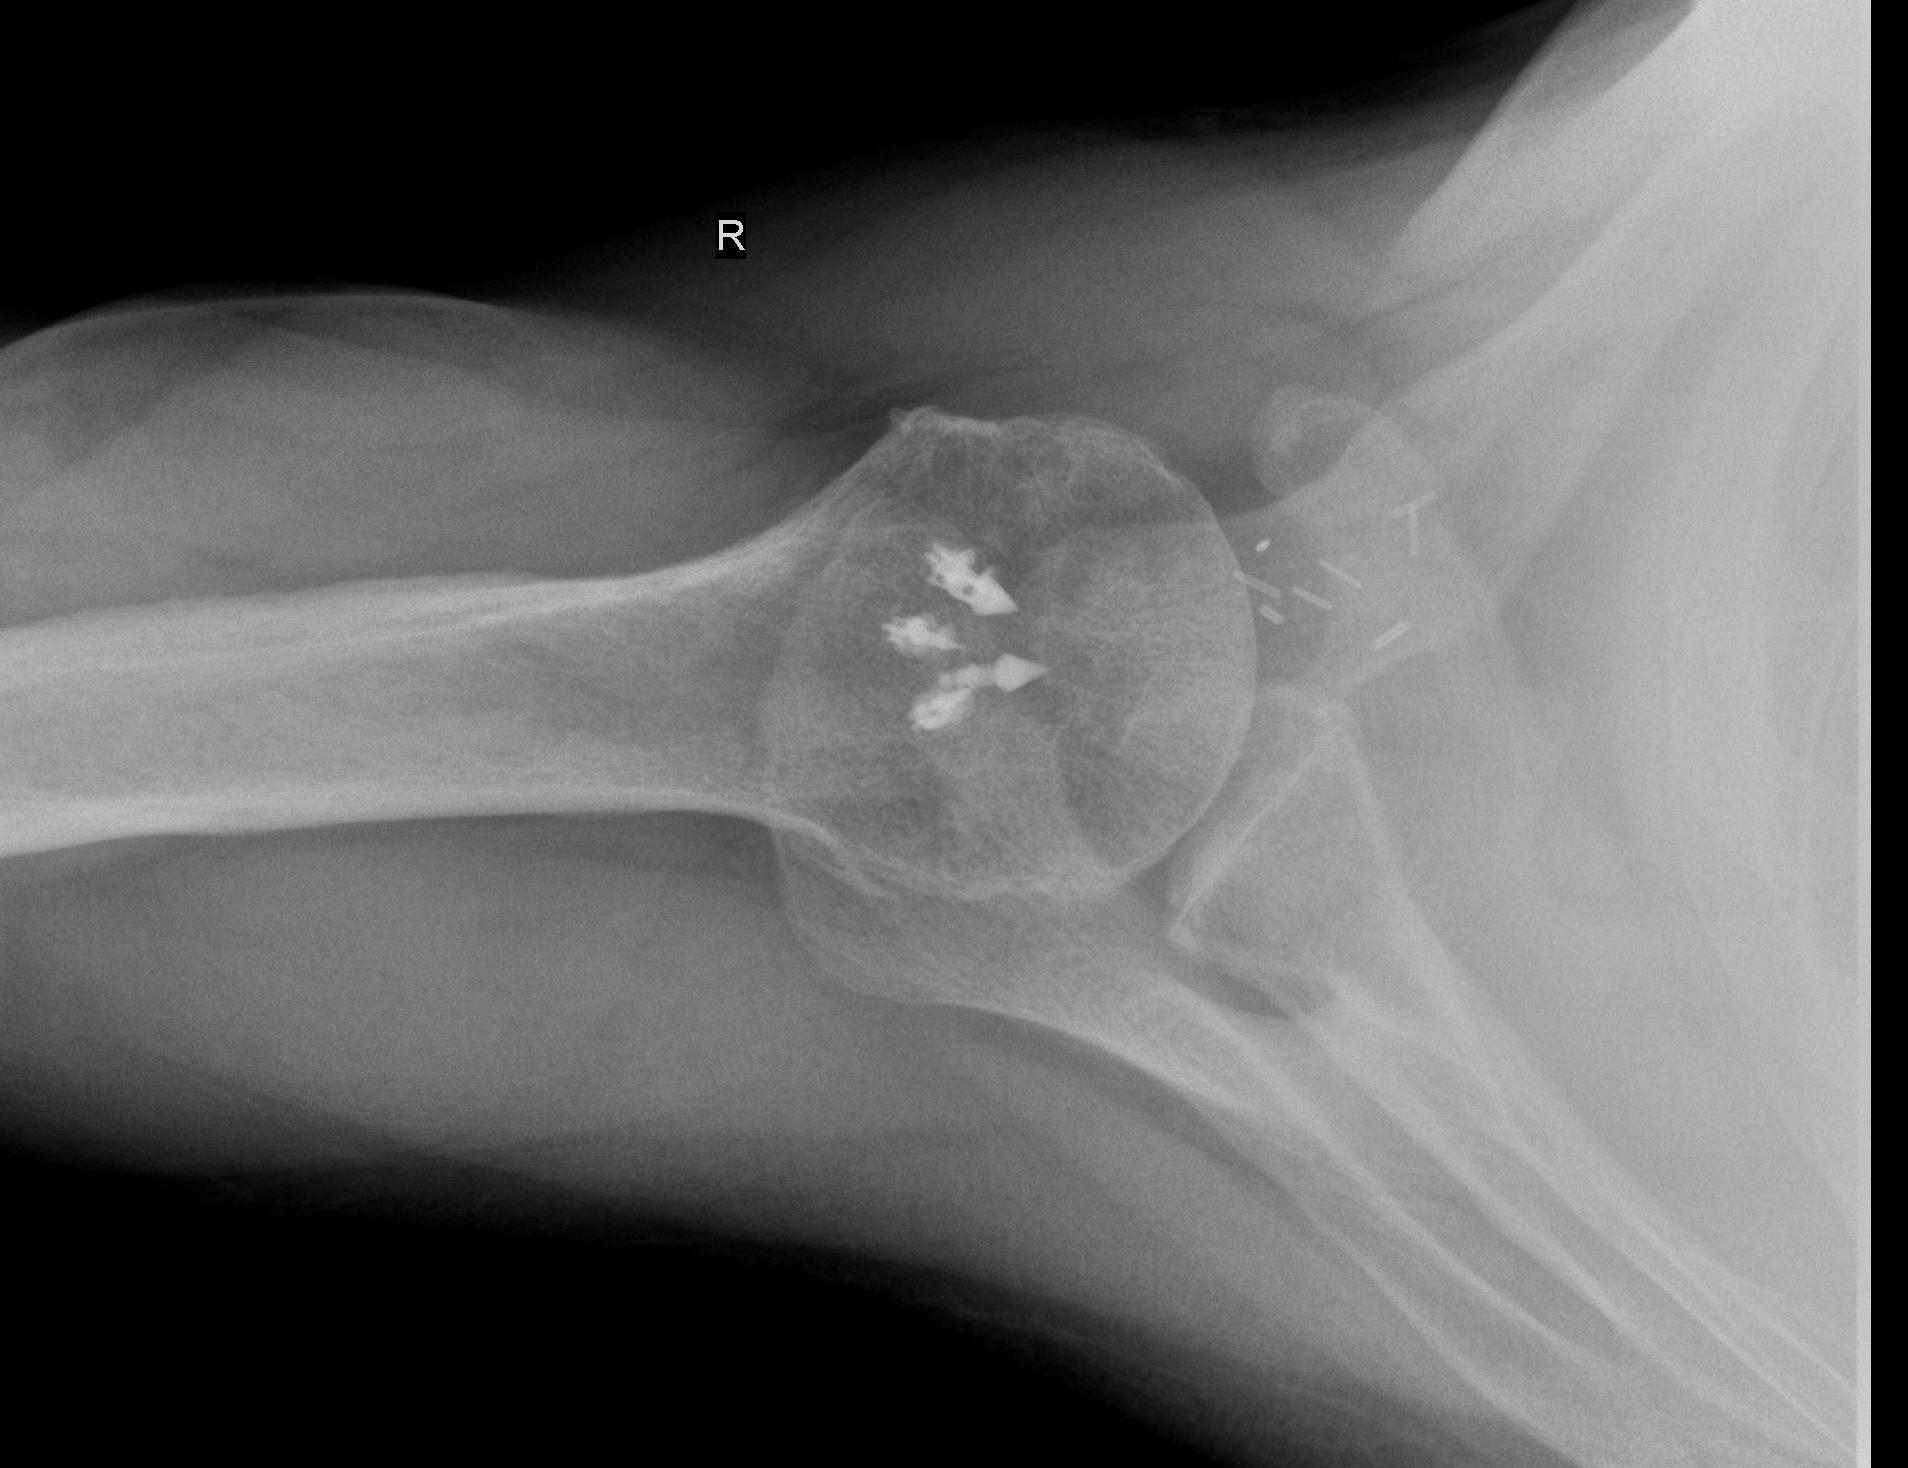

From www.azisks.com

Failed Rotator cuff repair with failure of bioscrew Arizona Are Screws Used In Rotator Cuff Surgery surgical techniques that may be used to repair a tear of the rotator cuff include arthroscopy, open surgery, or a. Some rotator cuff injuries may require surgery when nonsurgical treatments have not worked, but evidence suggests that nonsurgical. The surgery uses sutures or anchors to hold your tendon in place until your body. a rotator cuff repair is. Are Screws Used In Rotator Cuff Surgery.